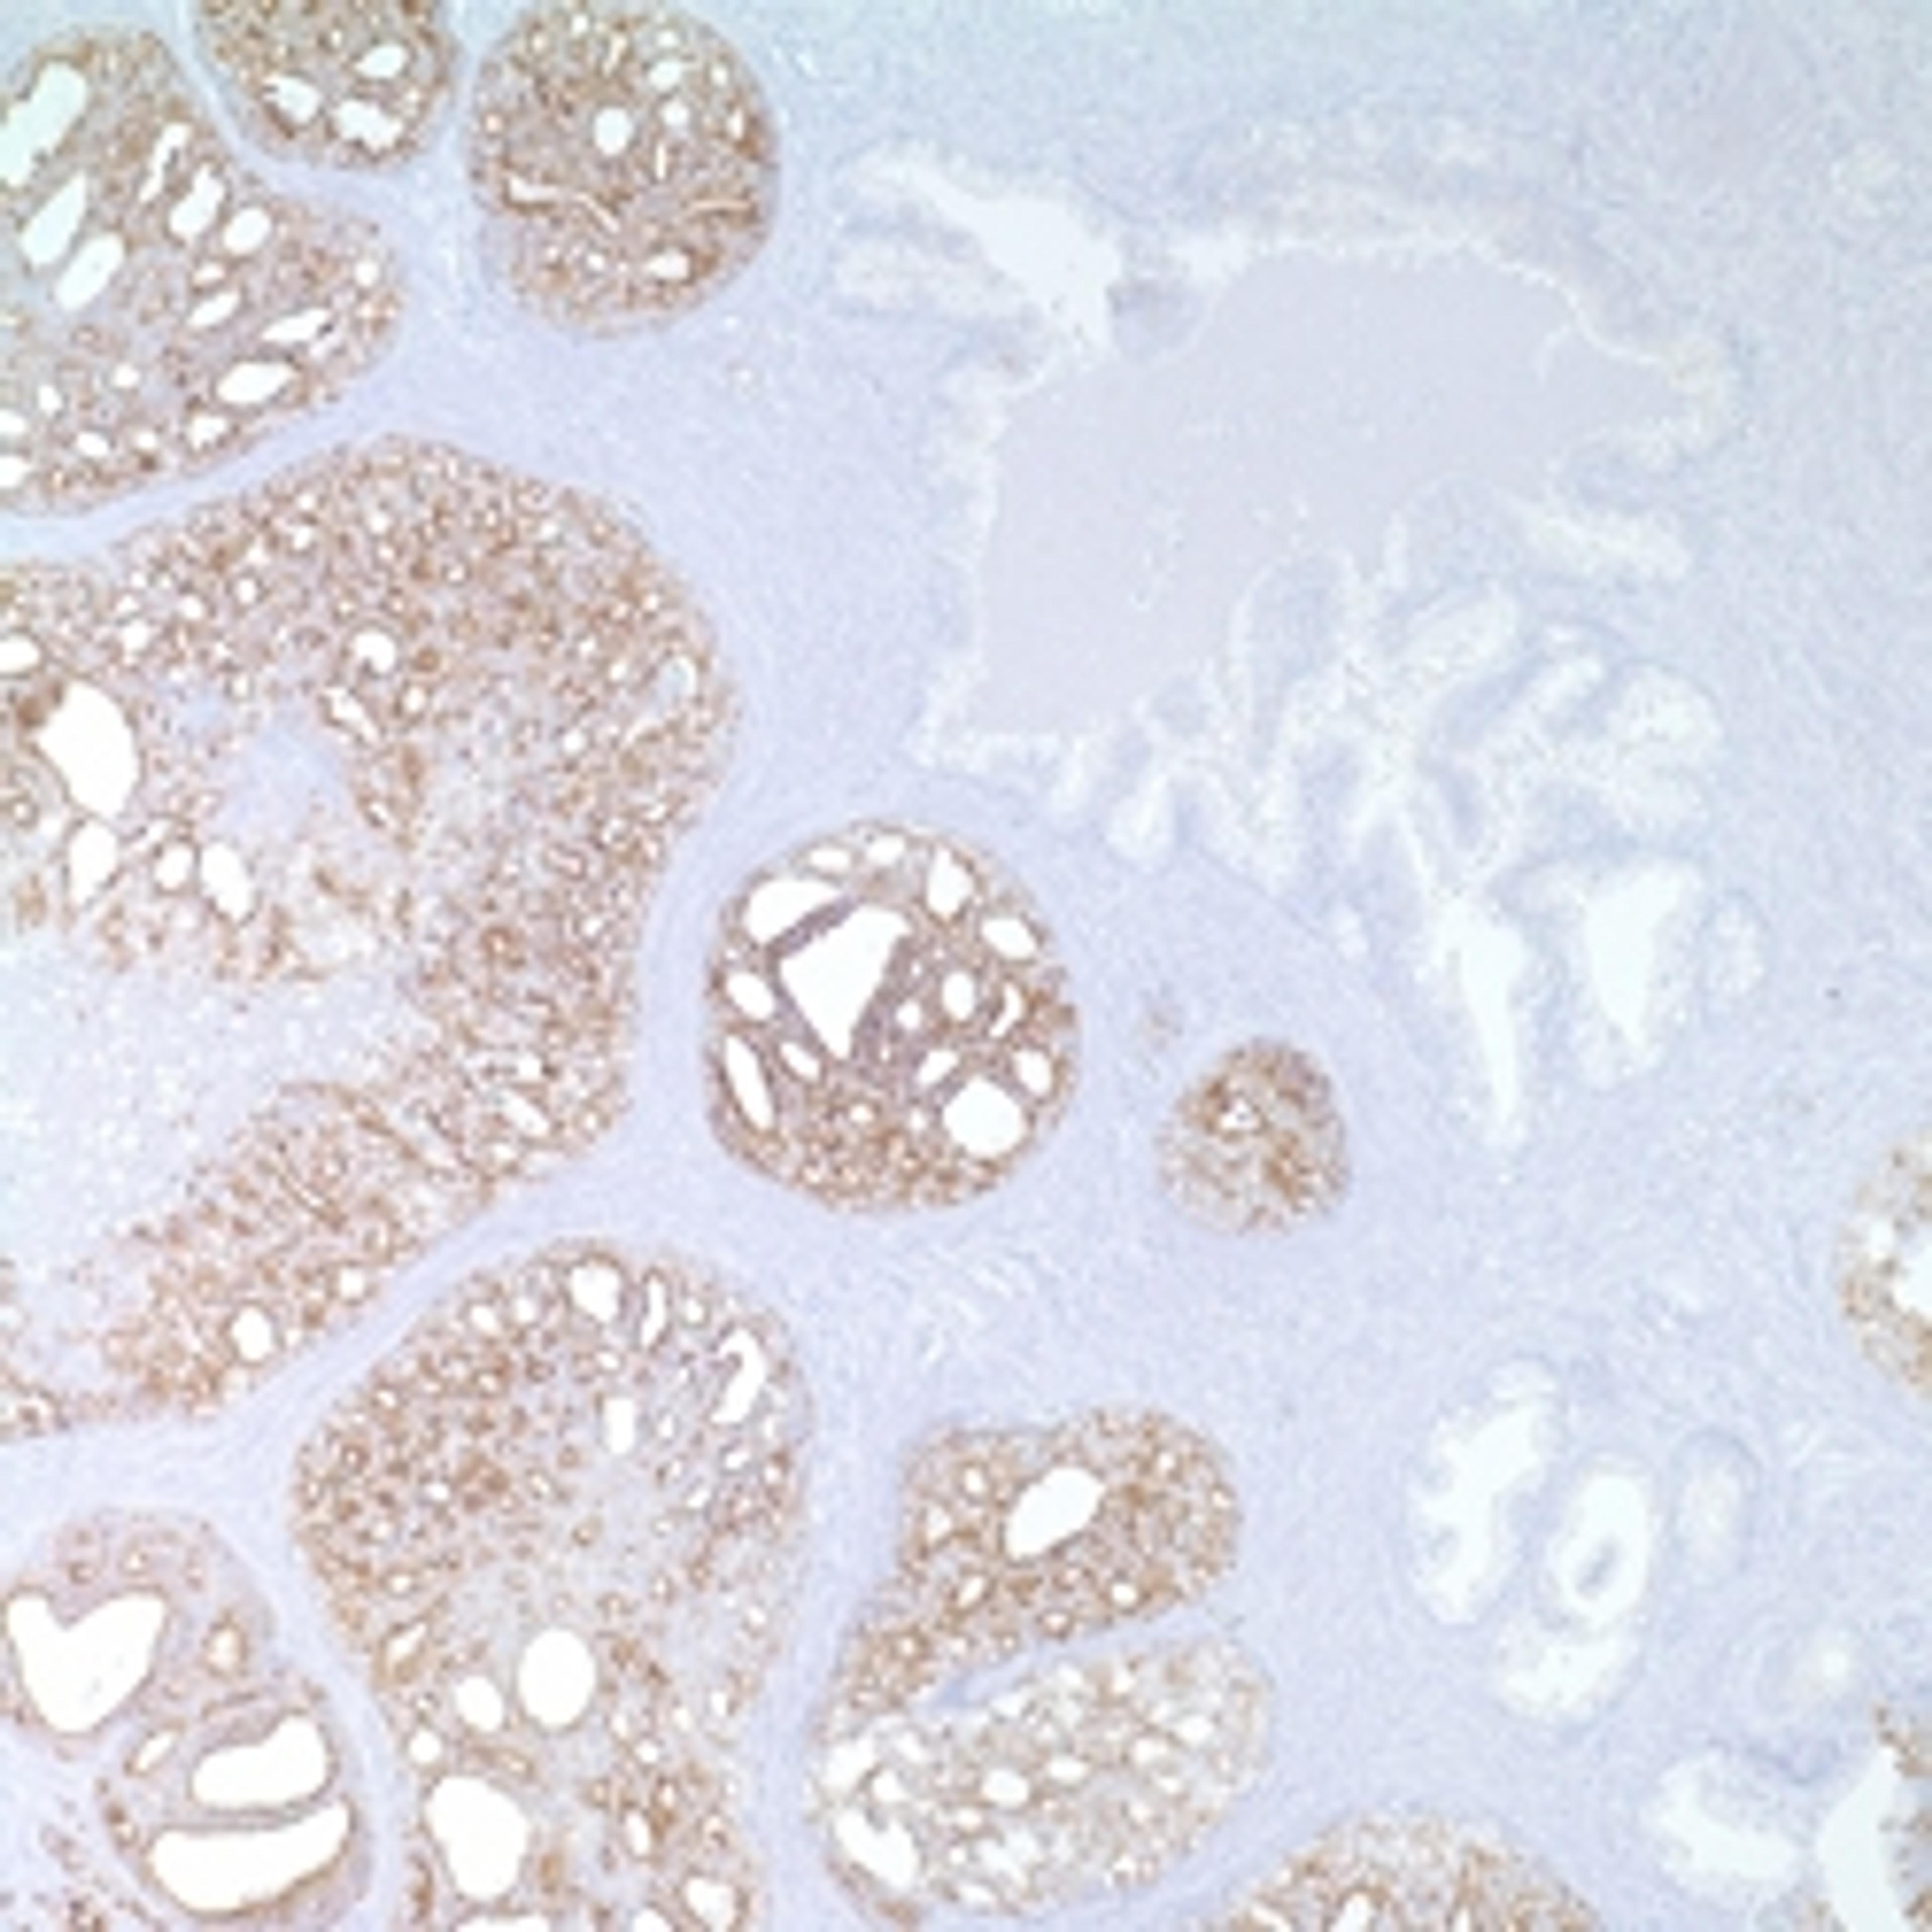

P504s (13H4)

Merck